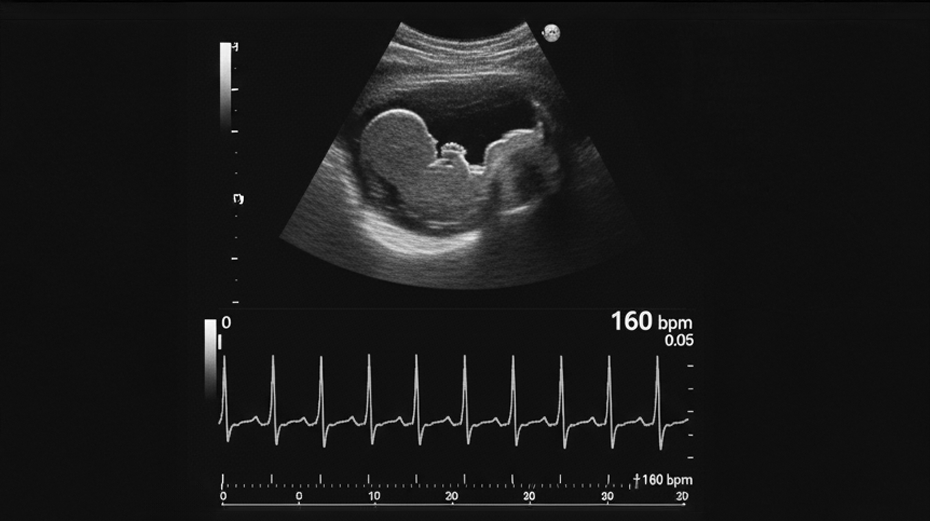

• Frecuencia Cardíaca Fetal

Translucencia Nucal Ductus Venoso Hueso Nasal Frecuencia Cardiaca Fetal